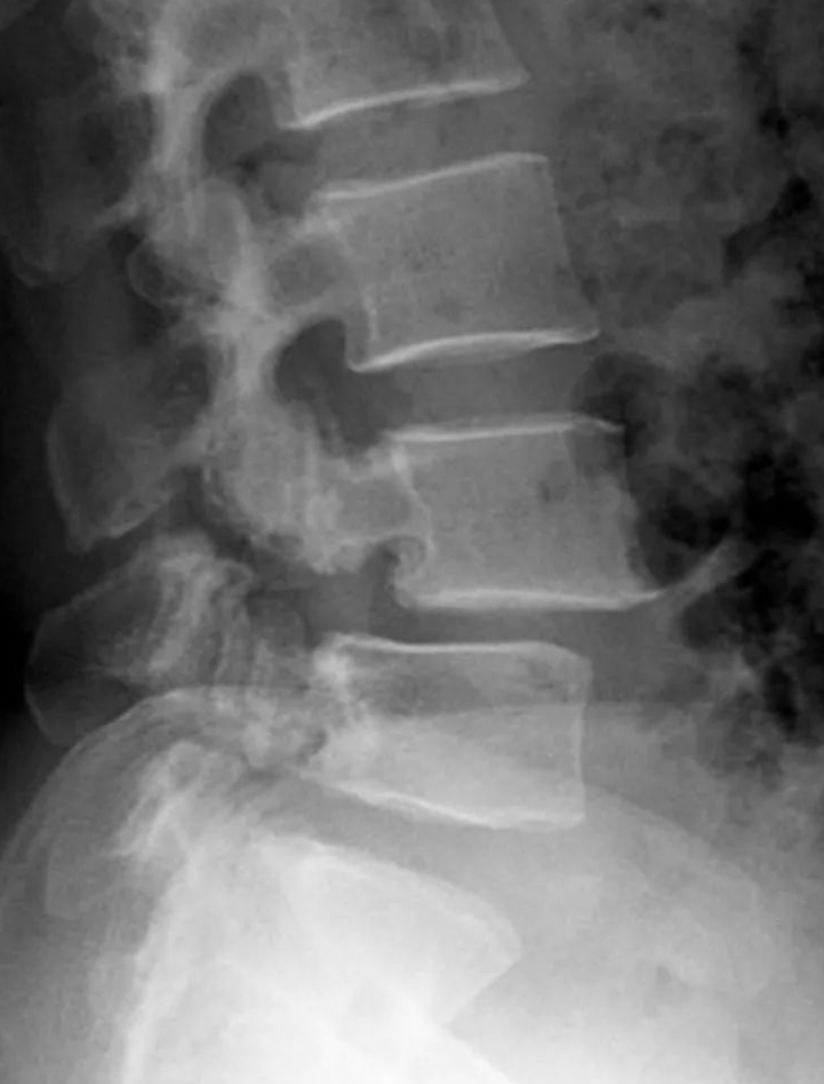

侧位片:椎弓根后下方细长或见透明裂隙,关节突间常见硬化征象;上位病变椎体出现滑移;椎间隙狭窄,椎间隙前后比例异常;可对滑脱程度进行具体测量。

图示:椎弓崩裂伴脊柱滑脱(侧位),第四腰椎椎弓崩裂,伴第四腰椎椎体向前滑脱,箭头示棘突后缘曲线异常。